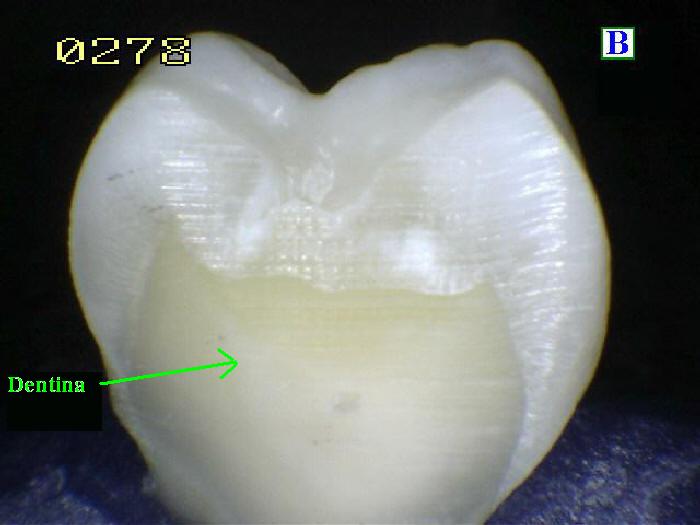

La

Dentina es la sustancia entre

el esmalte o cemento y la cámara pulpar. Es

secretada por los odontoblastos de la pulpa

dental. [13] La formación de dentina se conoce

como dentinogénesis. El material poroso de color

amarillo está compuesto por 70% de materiales

inorgánicos, 20% de materiales orgánicos y 10%

de agua en peso. [14] Debido a que es más suave

que el esmalte, se descompone más rápidamente y

está sujeto a caries severas si no se trata

adecuadamente, pero la dentina aún actúa como

una capa protectora y sostiene la corona del

diente.